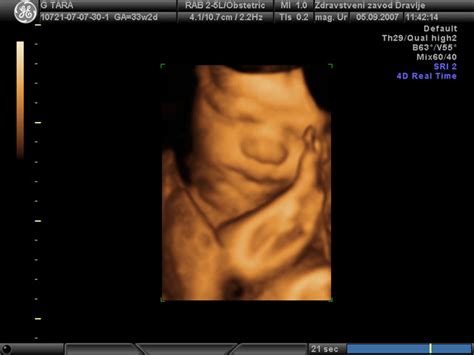

Z opazovanjem 4D ultrazvočne slike so britanski znanstveniki ugotovili, da se plod v 24. tednu starosti že lahko smeje. Pri 36. tednu starosti pa se lahko izraža skozi obrazne kretnje in dela različne mimike obraza, od spusta obrvi do namrščenega noska in širokega nasmeha. Dojenčki v maminem trebuhu pa tudi pogosto sesajo svoj prst in zehajo, kar so prav tako naučeni refleksi. Ti gibi niso le naključni; predstavljajo pomemben del razvoja možganov in živčnega sistema, saj otrok vadi različne izraze na obrazu. Ne gre samo za nasmeh, temveč znak, da možgani skozi živčni sistem pošljejo signale in to pomaga dojenčku, da se razvija.